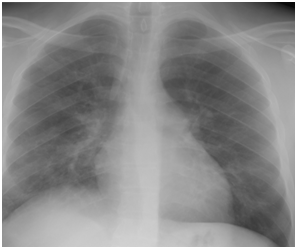

Figure 4C Follow up Chest X-ray three days after starting oseltamivir therapy.

Figure 4 H1N1 radiological pictures in a diabetic 28-year-old transplant recipient.